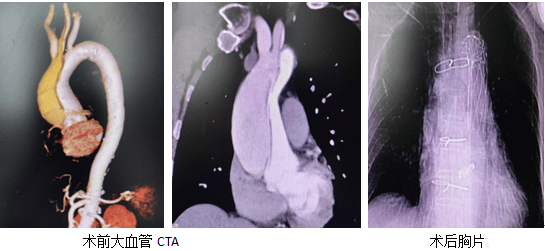

急查床旁超聲檢查驗證了她的推斷,之后立即前往CT室行大血管CTA后明確了診斷,主動脈夾層動脈瘤A型(II型),左頸總動脈撕裂嚴(yán)重,所以這就完全能驗證了他的頭暈癥狀,并且夾層撕裂至兩側(cè)冠脈口附近,破口多處。

打開心臟大血管后,血管撕裂嚴(yán)重,撕裂口圍繞冠脈口,周圍組織薄弱,主動脈瓣增厚關(guān)閉不全明顯,通向腦部血管夾層撕裂位置偏高且組織松脆,給手術(shù)增加了很大的難度。不過通過六個小時的手術(shù),所有困難迎刃而解,手術(shù)順利,患者轉(zhuǎn)危為安,術(shù)后頭暈癥狀消失,康復(fù)出院良好。